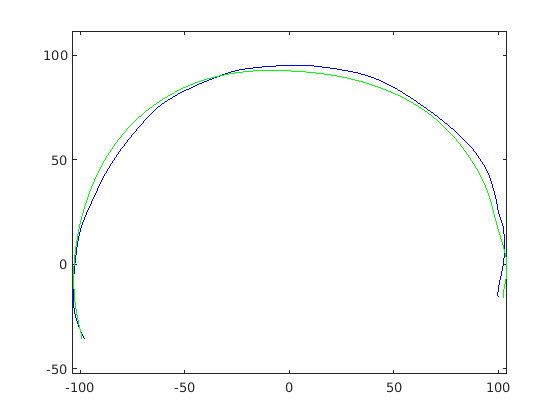

Figure 16 shows examples of the robust ellipse fit for four head profiles. The centre of the ellipse is used in a pose normalisation procedure where the ellipse centre is used as the origin of the profile and the angle from the ellipse centre to the nasion is fixed at -10 degrees. We call this Ellipse Centre - Nasion (ECN) pose normalisation and later compare this to GPA. The major and minor axes of the extracted ellipses are plotted as red and green lines respectively in Fig. 16.

|

|

|

|

Figure 17 shows all 100 profiles overlaid with the same alignment scheme. The median value of major ellipse axis and the ellipse centre-nasion angle differ by 3.6 degrees, so that when the nasion angle is fixed at -10 degrees, the median ellipse angle is -6.4 degrees (cf. -7.4 degrees with manual landmarking of the nasion). We noted regularity in the orientation of the fitted ellipse as is indicated by the clustering of the major (red) and minor (green) axes in Fig. 17 and the histogram of ellipse orientations in Fig. 18. For most people, the major axis of the ellipse is closely aligned with the y-axis (upright), and titled slightly forwards. A minority of heads (9%) in the training sample have their major ellipse axes closer to the vertical (these relatively tall and short heads are known as brachycephalic.) Ellipse axis clustering (relative to the fixed ellipse centre-nasion line) does not appear to be sharply defined. This is because many crania are close to circular in cross-section, making the orientation of these angles sensitive to small changes in shape from one person to the next. Note also the variation at the back of the head due to a variety of hair styles, some of which protrude from under the cap. We limit the region over which we model the cranial shape in order to crop this unwanted data out.